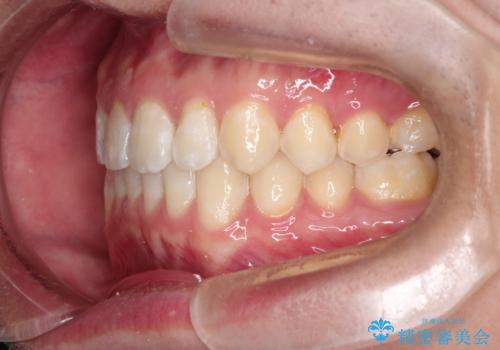

前歯がガタガタ インビザラインによる矯正

- 前歯がガタガタ、下の犬歯が飛び出ているのを主訴に来院されました。

下の奥歯を後方へ移動させてスペースを確保して、前歯を並べる計画としました。

目立たない装置をご希望されたので、インビザラインにて矯正治療を行いました。

使用時間を守っていただけたので、比較的スムーズに矯正を終了することができました。